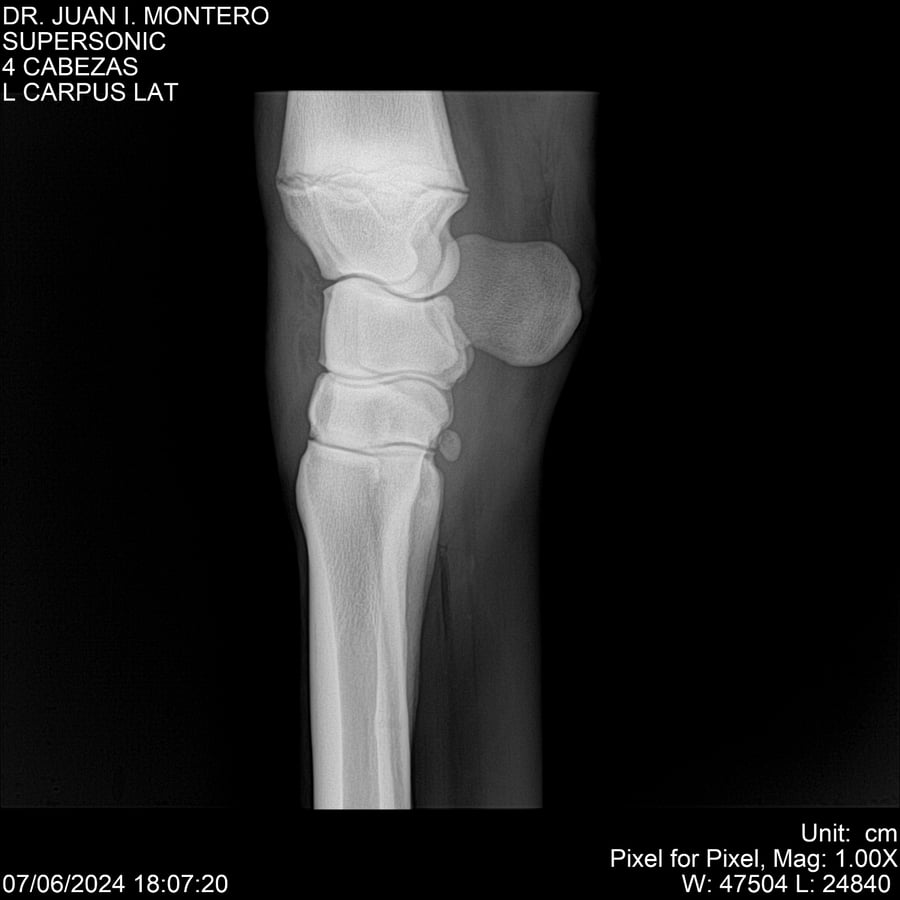

LOTE 5, SUPER SONIC Lote Anterior Volver al remate Lote Siguiente Ficha Contacto Montevideo - Ficha del Lote Identificador: #281089 Categoría: Yeguarizos Montevideo - 69 Visualizaciones ClicData Contacto Empresa: Abelenda N. R., Walter Hugo Nombre*: Teléfono* : E-mail* : Mensaje Enviar Registrese gratis Este contenido Exclusivo está disponible sólo para usuarios registrados Ingresar